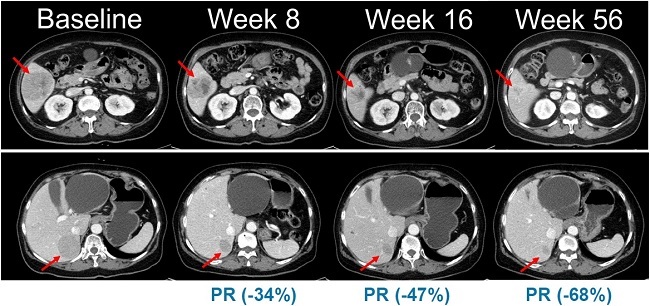

이번 임상 2상은 총 45명의 환자를 대상으로 표적 항암신약 벨바라페닙과 MEK 억제제인 코비메티닙(Cobimetinib) 병용요법의 유효성과 안전성을 평가하기 위한 다기관, 단일군 시험으로 진행된다.

한미약품이 최초로 개발한 벨바라페닙은 종양 세포의 성장과 증식에 관여하는 미토겐 활성화 단백질 키나아제(mitogen-activated protein kinases, MAPK) 경로 중 RAF 및 RAS 유전자 돌연변이를 타깃해 억제하는 경구용 표적 항암제다.

벨바라페닙은 RAF 이합체(dimer)를 선택적으로 저해하는 차별화된 기전을 토대로 BRAF ClassⅡ/Ⅲ 변이와 RAS 변이를 보유한 종양을 표적한다. 기존 BRAF 저해제가 주로 단일체(monomer)만을 억제하는 것과 달리, 벨바라페닙은 BRAF 및 CRAF 이합체까지 함께 억제하도록 설계돼 RAF 이합체 형성에 따른 내성 문제를 극복할 수 있도록 개발됐다.

이에 따라 벨바라페닙과 코비메티닙의 병용요법은 기존 BRAF 단일체와 MEK 억제제 병용 치료의 기전적 한계를 극복하고, 보다 폭넓은 유전자 변이 환자군에서 임상적 이점을 제공할 수 있는 치료 전략으로 평가된다.